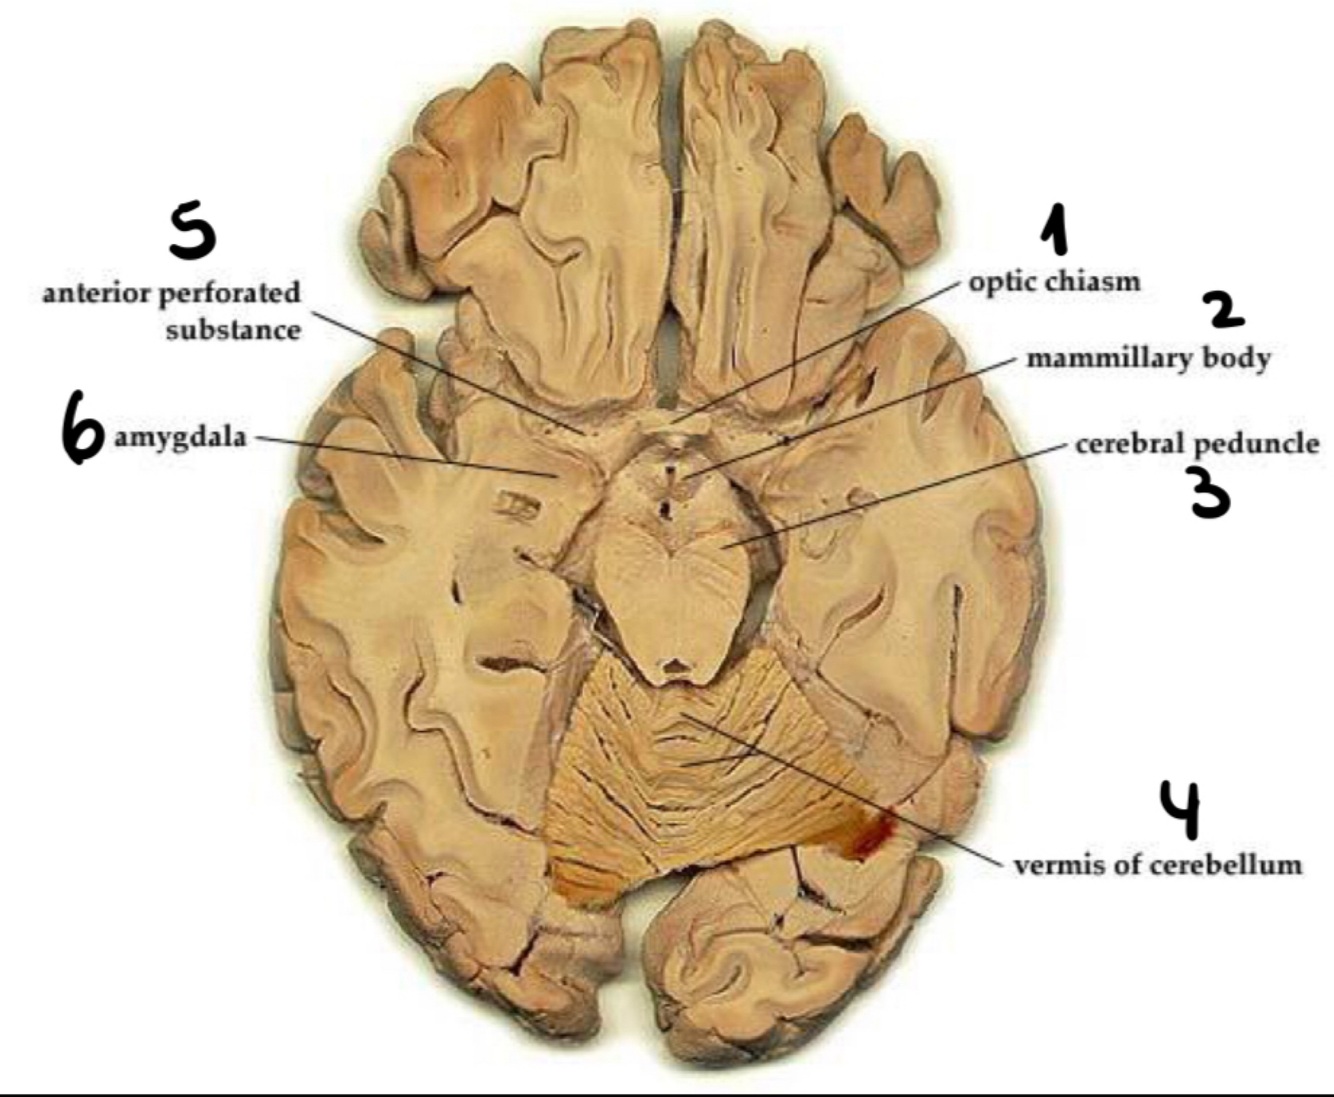

Tumours can compress the optic chiasm (loss of vision)